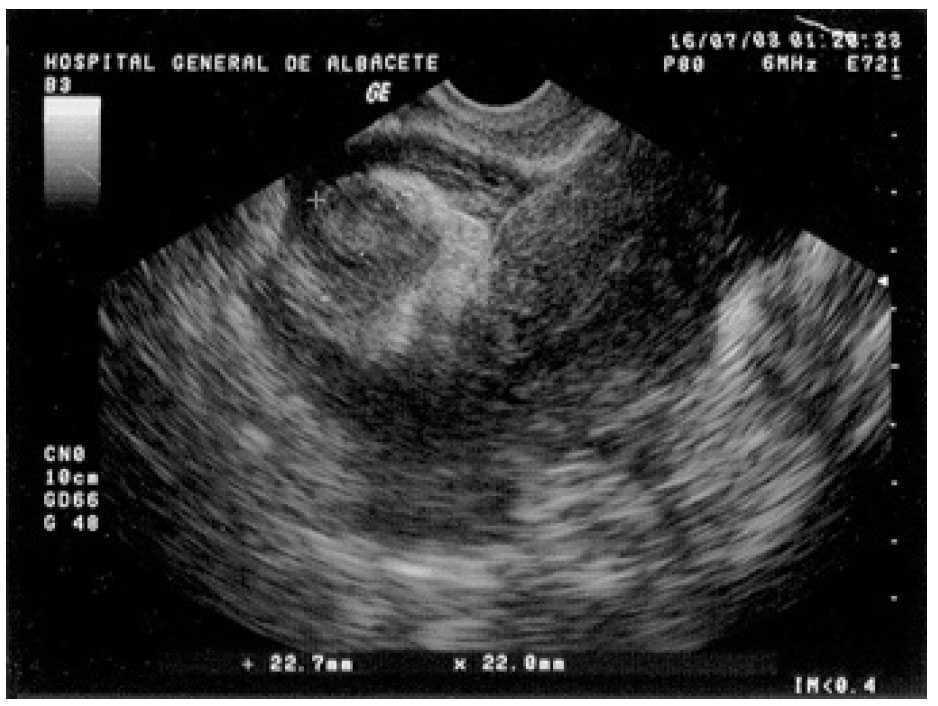

A la exploración presentaba una presión arterial de 90/55 mmHg y una temperatura de 37 °C; el abdomen era blando y depresible, con dolor a la palpación profunda en el hipogastrio y ambas fosas ilíacas, sin signos de irritación peritoneal. La movilización cervical no era dolorosa y el útero y los anejos no fueron delimitables por defensa de la paciente. En la analítica destacó una hemoglobina de 10,2 g/dl y un hematocrito del 30,6%; el resto del hemograma, las pruebas de coagulación y la bioquímica resultaron normales. La ecografía vaginal mostró un útero en anteflexión, de tamaño normal, con un endometrio lineal y una pequeña cavidad real, sin estructuras gestacionales en su interior y rodeado por una moderada cantidad de líquido libre y coágulos (fig. 1). Ambos ovarios eran normales y por encima del derecho se visualizaba una imagen redondeada, heterogénea, de 22,7 × 22 mm de diámetro (fig. 2), que se observó también en la ecografía ginecológica abdominal previa.

Figura 2. Ecografía transvaginal en la que se visualiza una formación redondeada heterogénea de 22,7 × 22 mm, localizada por encima del anejo derecho.